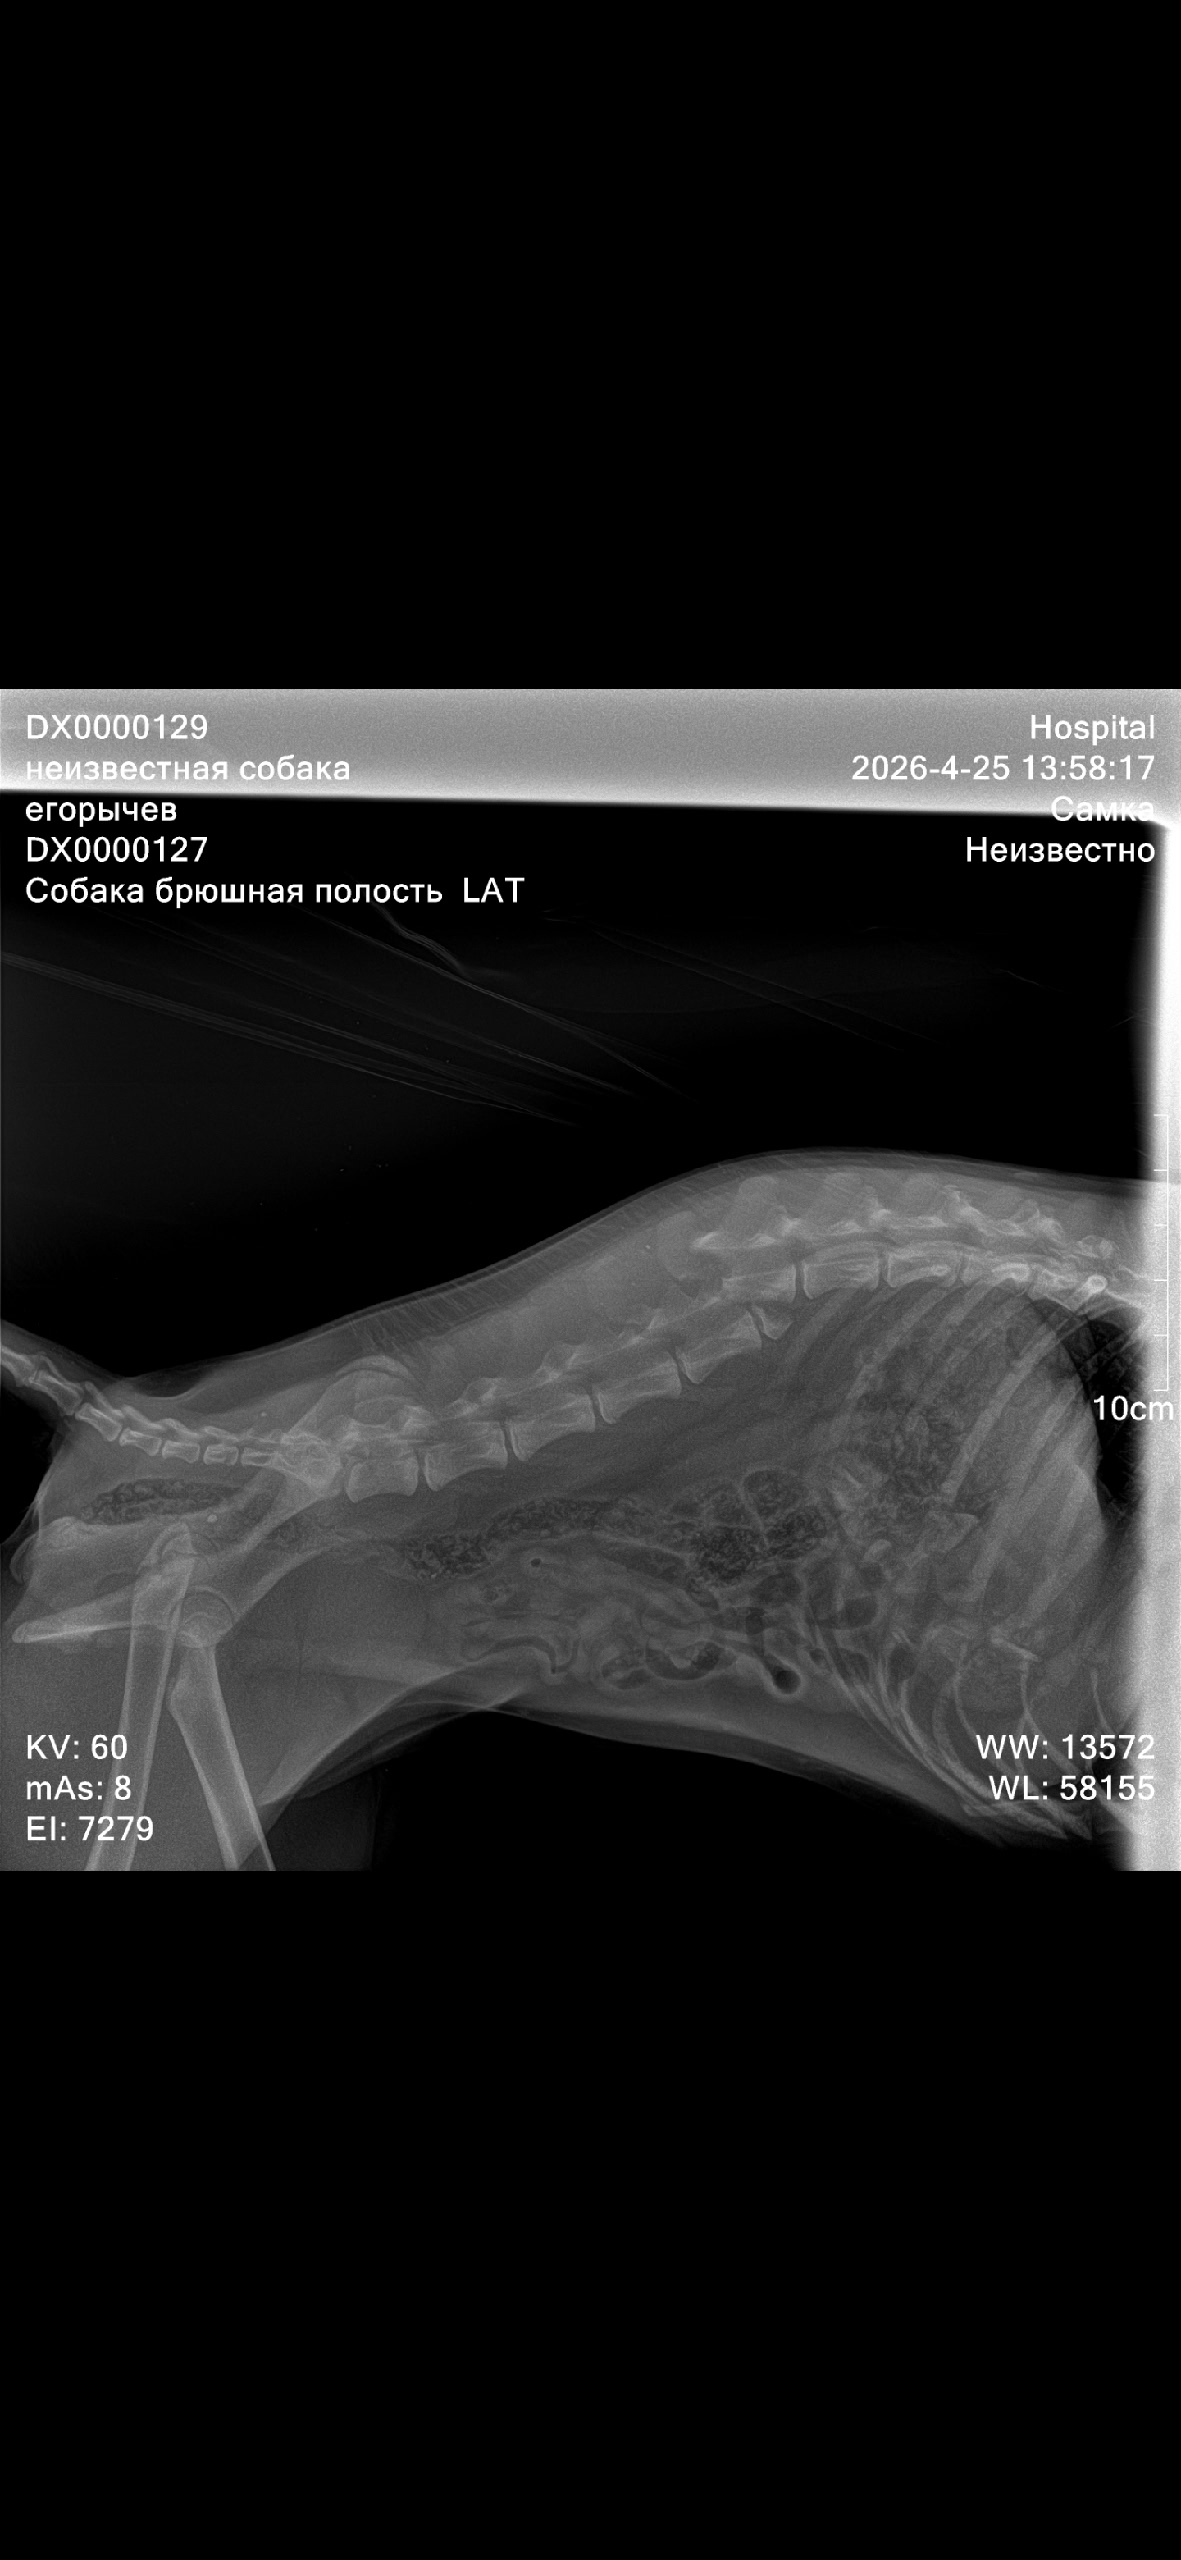

Снимок показал полный перелом позвоночника. При этом возраст животного — 11 месяцев. Череповчанин решил попытаться дать молодой собаке шанс на жизнь. За два дня он собрал большую сумму на операцию — в районе 150 тысяч рублей. К истории подключились зооволонтеры и тысячи неравнодушных горожан.

Сегодня мужчина возил животное на обследование в Вологду, а уже в среду назначена операция. Она продлится 4 часа. Ветврачи отмечают: шансы высокие, но, к сожалению, собака останется инвалидом.